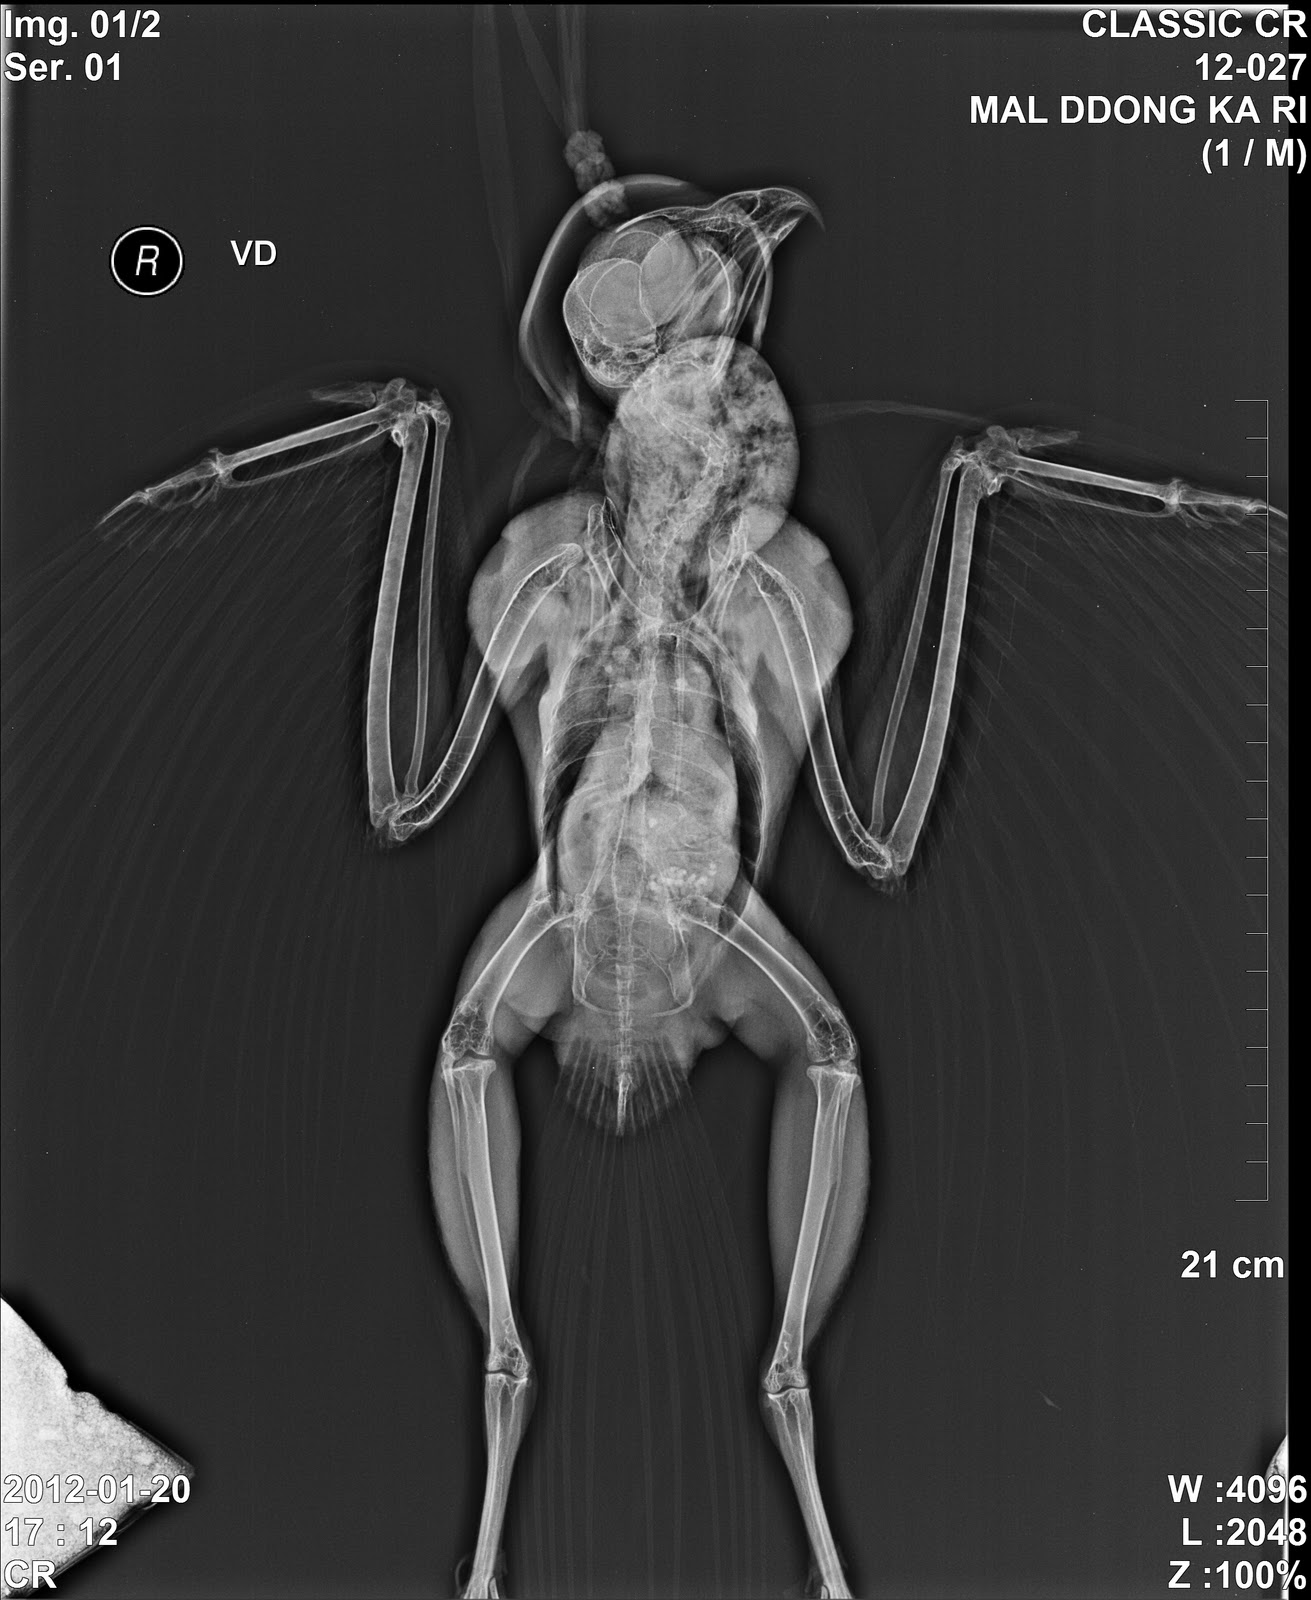

요즘들어 말똥가리들의 중독사고가 자주 발생하고 있는데, 이 녀석은 나이가 좀 든 수컷 말똥가리였죠.

근위와 소낭에 식이물이 확인되었고, 이를 제거하기로 하였습니다.

| 잘 보시면 위 내에 새의 다리가 보일 겁니다. |